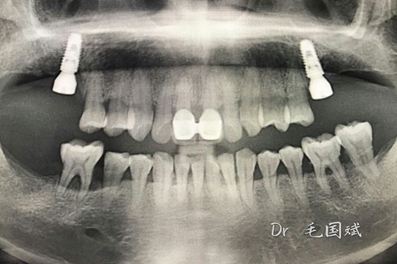

毛國斌種植病例——群討論分享